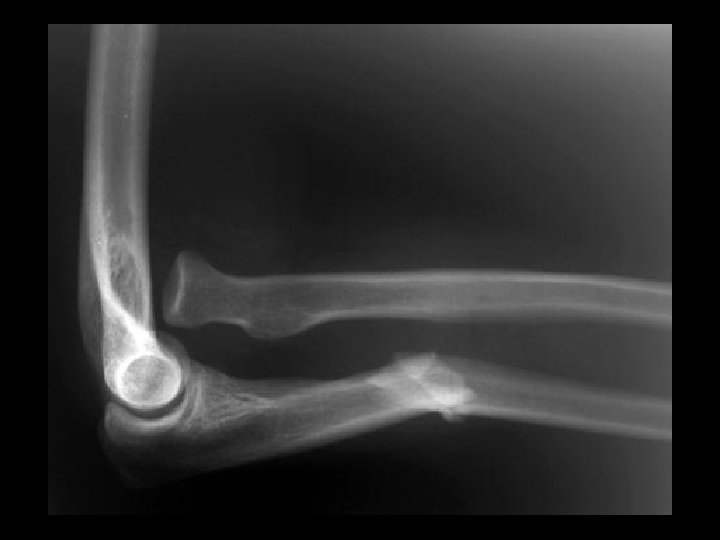

Rheumatoid Arthritis • Findings: – Deformed elbow joint due to complete loss of articular cartilage and large erosions – Soft tissue pannus within the joint • ddx: – NONE! – This is an Aunt Minnie!